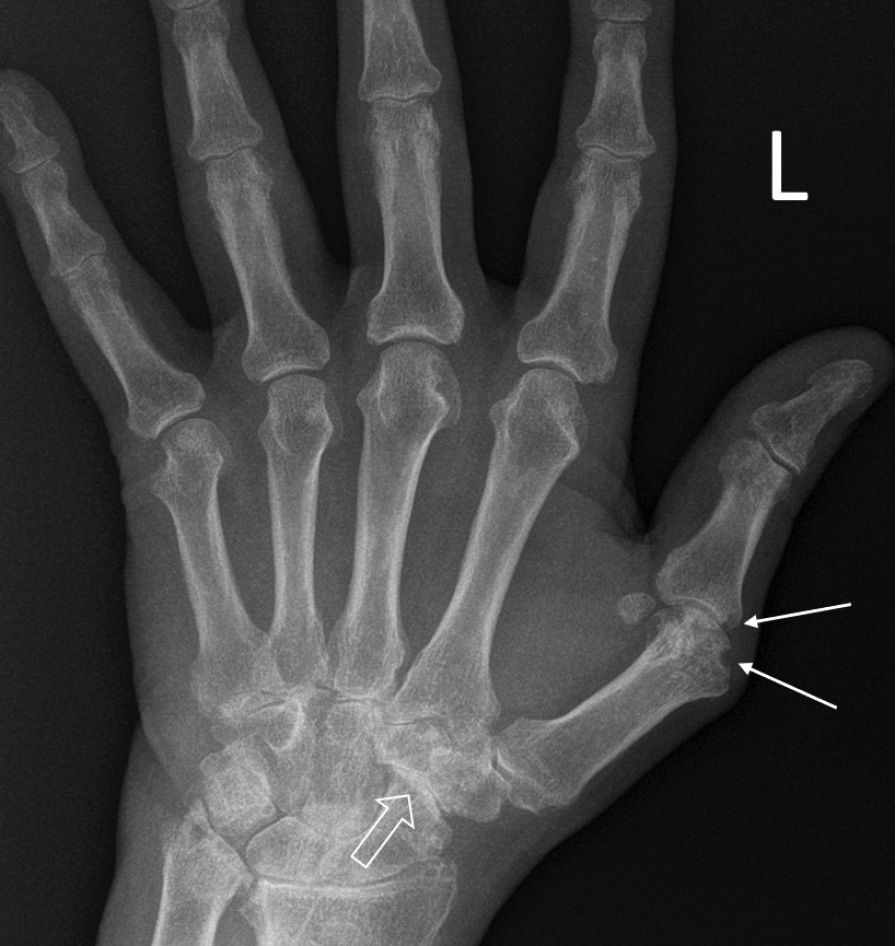

При компьютерной томографии органов грудной клетки данных за «свежие» очаговые и инфильтративные изменения не получено. Увеличения лимфатических узлов подмышечных областей, средостения, корней легких не выявлено. Отмечался усиленный грудной кифоз, обызвествление передней продольной связки, на всем уровне исследования определялись передне-боковые спондилофиты, а также анкилоз большинства реберно-поперечных суставов. По данным рентгенографии кистей (рис. 1, 2) и стоп (рис. 3, 4) диагностированы признаки эрозивного артрита, анкилоз суставов запястья. По данным МРТ крестцово-подвздошных суставов (КПС) определялся неравномерный анкилоз КПС, хрящи по суставным поверхностям неравномерной толщины, примерно на половине протяжении сустава отсутствуют, «суставной промежуток» облитерирован. Неравномерность и нечеткость контура суставных поверхностей за счет множества краевых эрозий справа, единичных – слева, с наличием остеокластоза, в нижнем отделе слева по смежным отделам определяются участки трабекулярного отека, данная находка клинически интерпретирована как двусторонний активный сакроилиит (рис. 5, 6).

Рис. 1. Рентгенограмма левой кисти в прямой проекции. Краевые эрозии суставных поверхностей первого пястно-фалангового сустава (тонкие стрелки), сужение суставных щелей суставов запястья с формированием анкилозов (толстая стрелка)

В возрасте 40 лет присоединились жалобы на симметричные воспалительные боли в лучезапястных суставах и мелких суставах кистей, резкое снижение объема движения в лучезапястных суставах. При осмотре пациента выявлено: число болезненных суставов – 7, число припухших суставов – 4, положительный симптом поперечного сжатия кистей и стоп, ульнарная девиация мелких суставов стоп. Резко сниженный объем движения в лучезапястных суставах обеих кистей. По данным рентгенологического обследования зафиксированы типичные изменения для РА: резкое неравномерное выраженное сужение суставных щелей, субхондральный склероз в лучезапястных суставах, анкилоз в суставах запястья, пястно-запястных, пястно-фаланговых и межфаланговых суставах. Краевые эрозии оснований основных фаланг двух пальцев; участки кистовидной перестройки костной ткани. Локальное утолщение мягких тканей. При лабораторном обследовании пациента отмечен положительный ревматоидный фактор, высокий титр антицитруллинированных антител, повышение острофазовых белков.